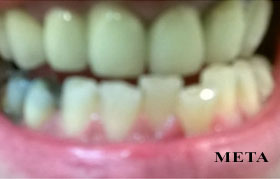

PHOTO GALLERY